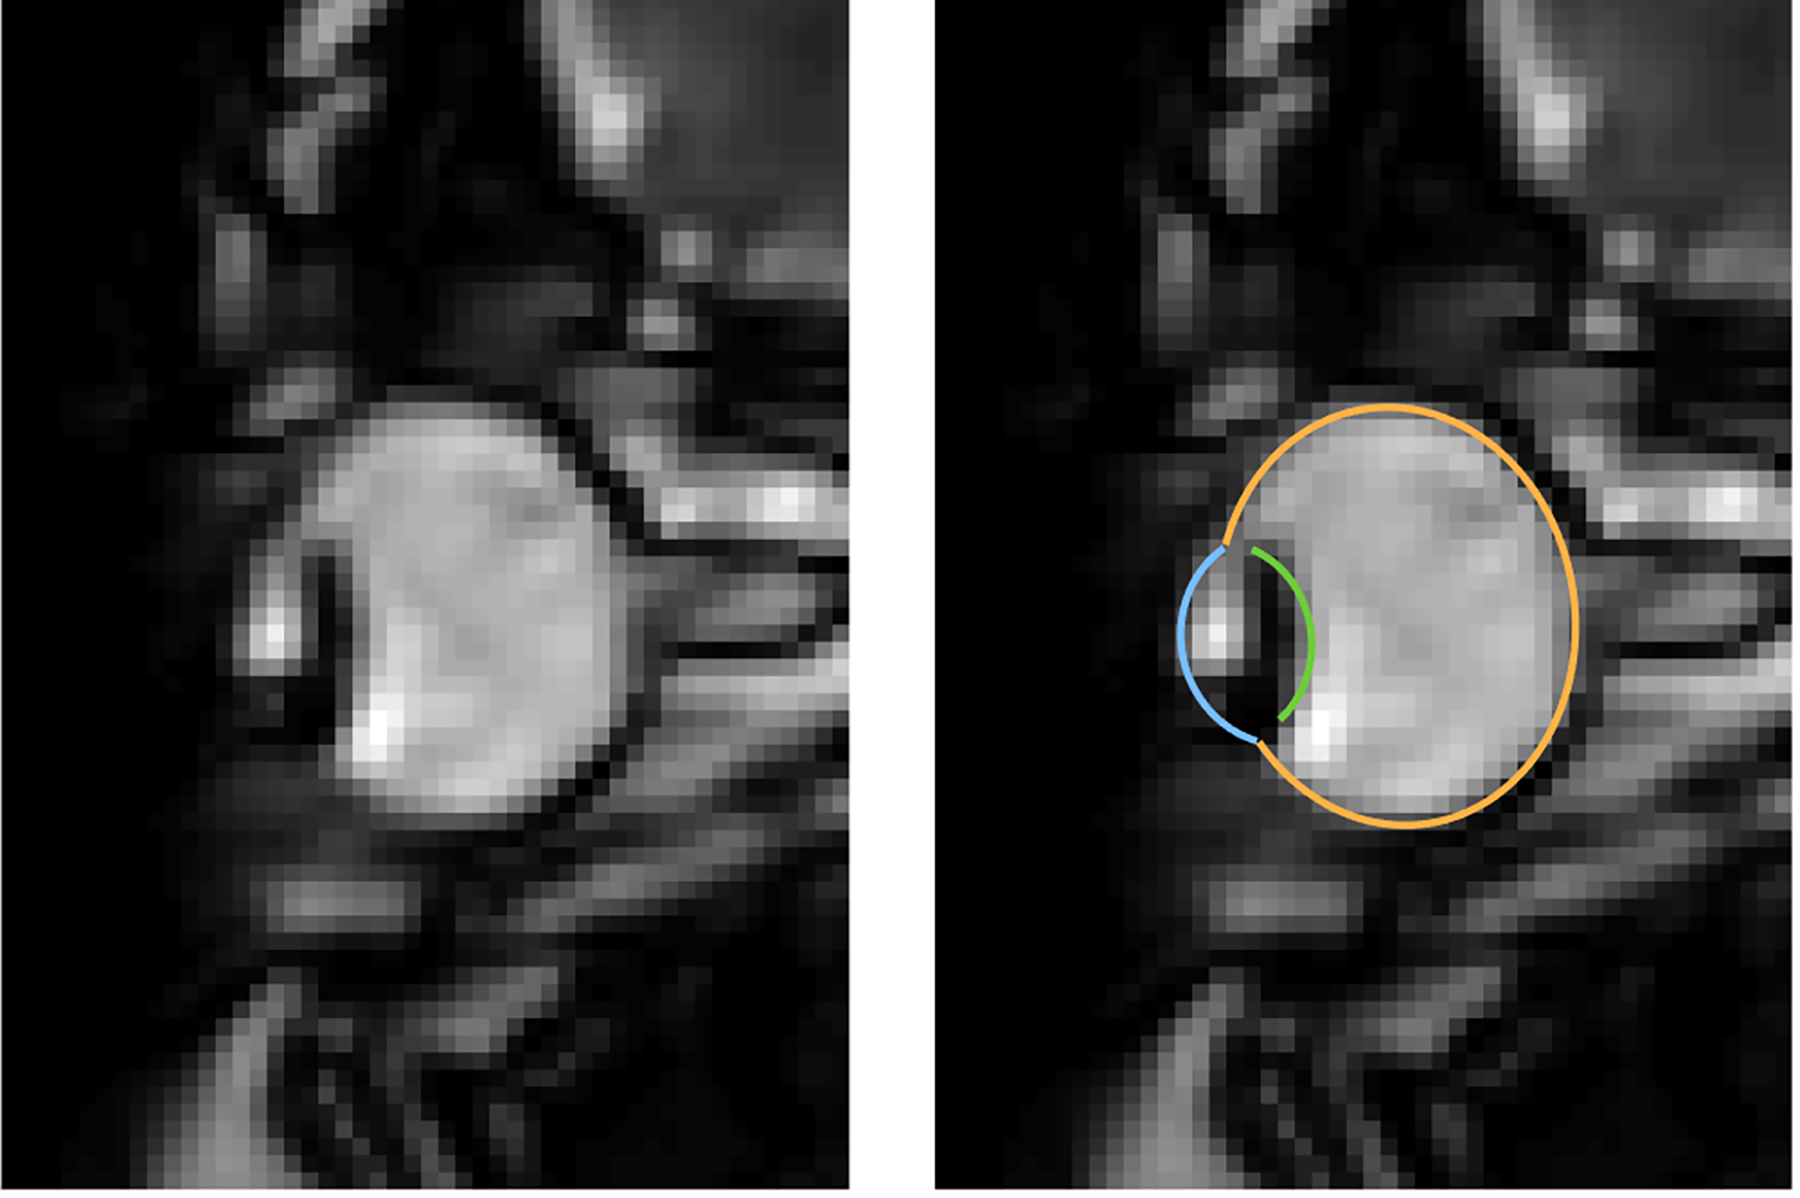

Forscher der Westfälischen Wilhelms-Universität (WWU) Münster konnten zum ersten Mal die vollständige Augenbewegung beim Blinzeln messen. Die Analyse der Augenbewegung beruht auf der Magnetresonanztomographie (MRT), die einen Querschnitt und nicht nur den vorderen Teil des Auges vermisst. Dies ermöglicht erstmals Messungen bei geschlossenem Auge, die zusätzliche Betrachtung der Augenmuskulatur und komplette Verschiebungen oder Deformationen des Augapfels zu messen. Die Studie über das neu entwickelte Verfahren ist in der Fachzeitschrift „eNeuro“ erschienen.

Augenbewegungen werden typischerweise mit sogenannten Eyetrackern gemessen, also Hochgeschwindigkeitskameras, die die Position der Pupille filmen. Einige Aspekte von Augenbewegungen lassen sich damit jedoch nicht messen. „Es ist uns gelungen, ein Verfahren zu entwickeln, das Augenbewegungen in bisher unerreichter zeitlicher Auflösung mit Echtzeit-MRT-Sequenzen misst. So konnten wir mit unserer Methode zum Beispiel zeigen, dass der komplette Augapfel beim Blinzeln in die Augenhöhle zurückgezogen wird“, erläutert Autor Johannes Kirchner, wissenschaftlicher Mitarbeiter am Institut für Psychologie der WWU. Die Methode haben die WWU-Wissenschaftler mit der Co-Autorin Prof. Dr. Tamara Watson von der Western Sydney University entwickelt.

MRT ist ein relativ langsames Verfahren, die zeitliche Auflösung bewegt sich normalerweise im Bereich von Sekunden oder Minuten. Augenbewegung hingegen sind schnell und dauern typischerweise nur ein paar Dutzend Millisekunden an. Entwicklungen in den vergangenen zehn Jahren haben es jedoch ermöglicht, 2-D-MRT-Aufnahmen mit bis zu 20 Millisekunden zeitlicher Auflösung zu produzieren. Diese ultraschnellen Verfahren kommen vor allem bei der Herzbildgebung zum Einsatz und werden bislang nicht auf die Messung von Augenbewegungen angewandt. „In unseren Aufnahmen haben wir eine zeitliche Auflösung von etwa 35 Millisekunden erzielt. Da bei einer gesamten Messzeit von ein paar Minuten mehr als 10.000 Bilder entstehen, braucht man, um tatsächliches Eyetracking zu betreiben, einen vollautomatischen Algorithmus, um diese Daten auszuwerten“, schildert Mitautor Prof. Dr. Markus Lappe, Leiter des Lehrstuhls für Allgemeine Psychologie und kognitive Neurowissenschaften am Institut für Psychologie der WWU. „Mit ‚MREyeTrack’ haben wir einen solchen sogenannten Segmentierungsalgorithmus entwickelt, der es erstmals ermöglicht, vollautomatisch Position und Orientierung des Auges in jedem einzelnen Bild zu analysieren.“